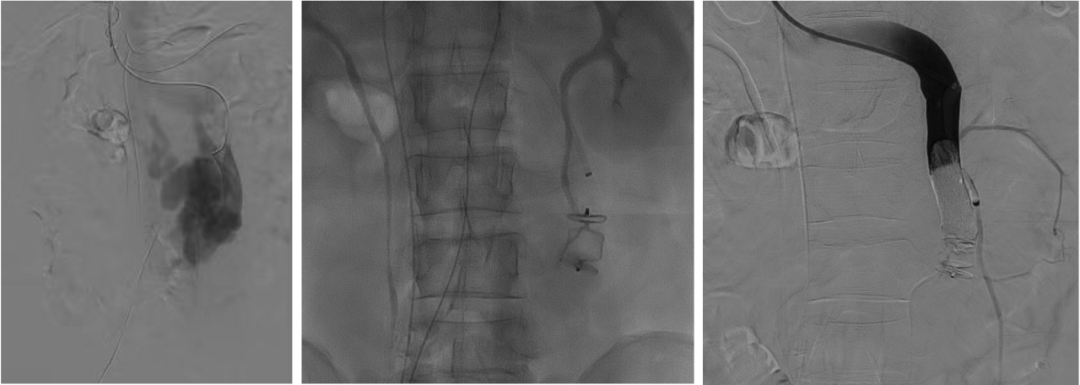

至腸系膜上動脈行間接門靜脈造影,未見門靜脈顯影,可見巨大異常分流道,遂至脾動脈行間接門脈造影可見門靜脈異常纖細,腸系膜下靜脈見異常分流道形成

以微導管行肝動脈標記輔助穿刺,門靜脈造影顯示血流呈離肝狀態(tài)

超選至腸系膜下靜脈異常分流道,予以栓塞18mm的Amplatzer vascular plug及適量25%生物膠,造影示異常分流道消失

8mm覆膜支架釋放于肝內(nèi)穿刺道,考慮門脈纖細,遂以6mm球囊后擴張